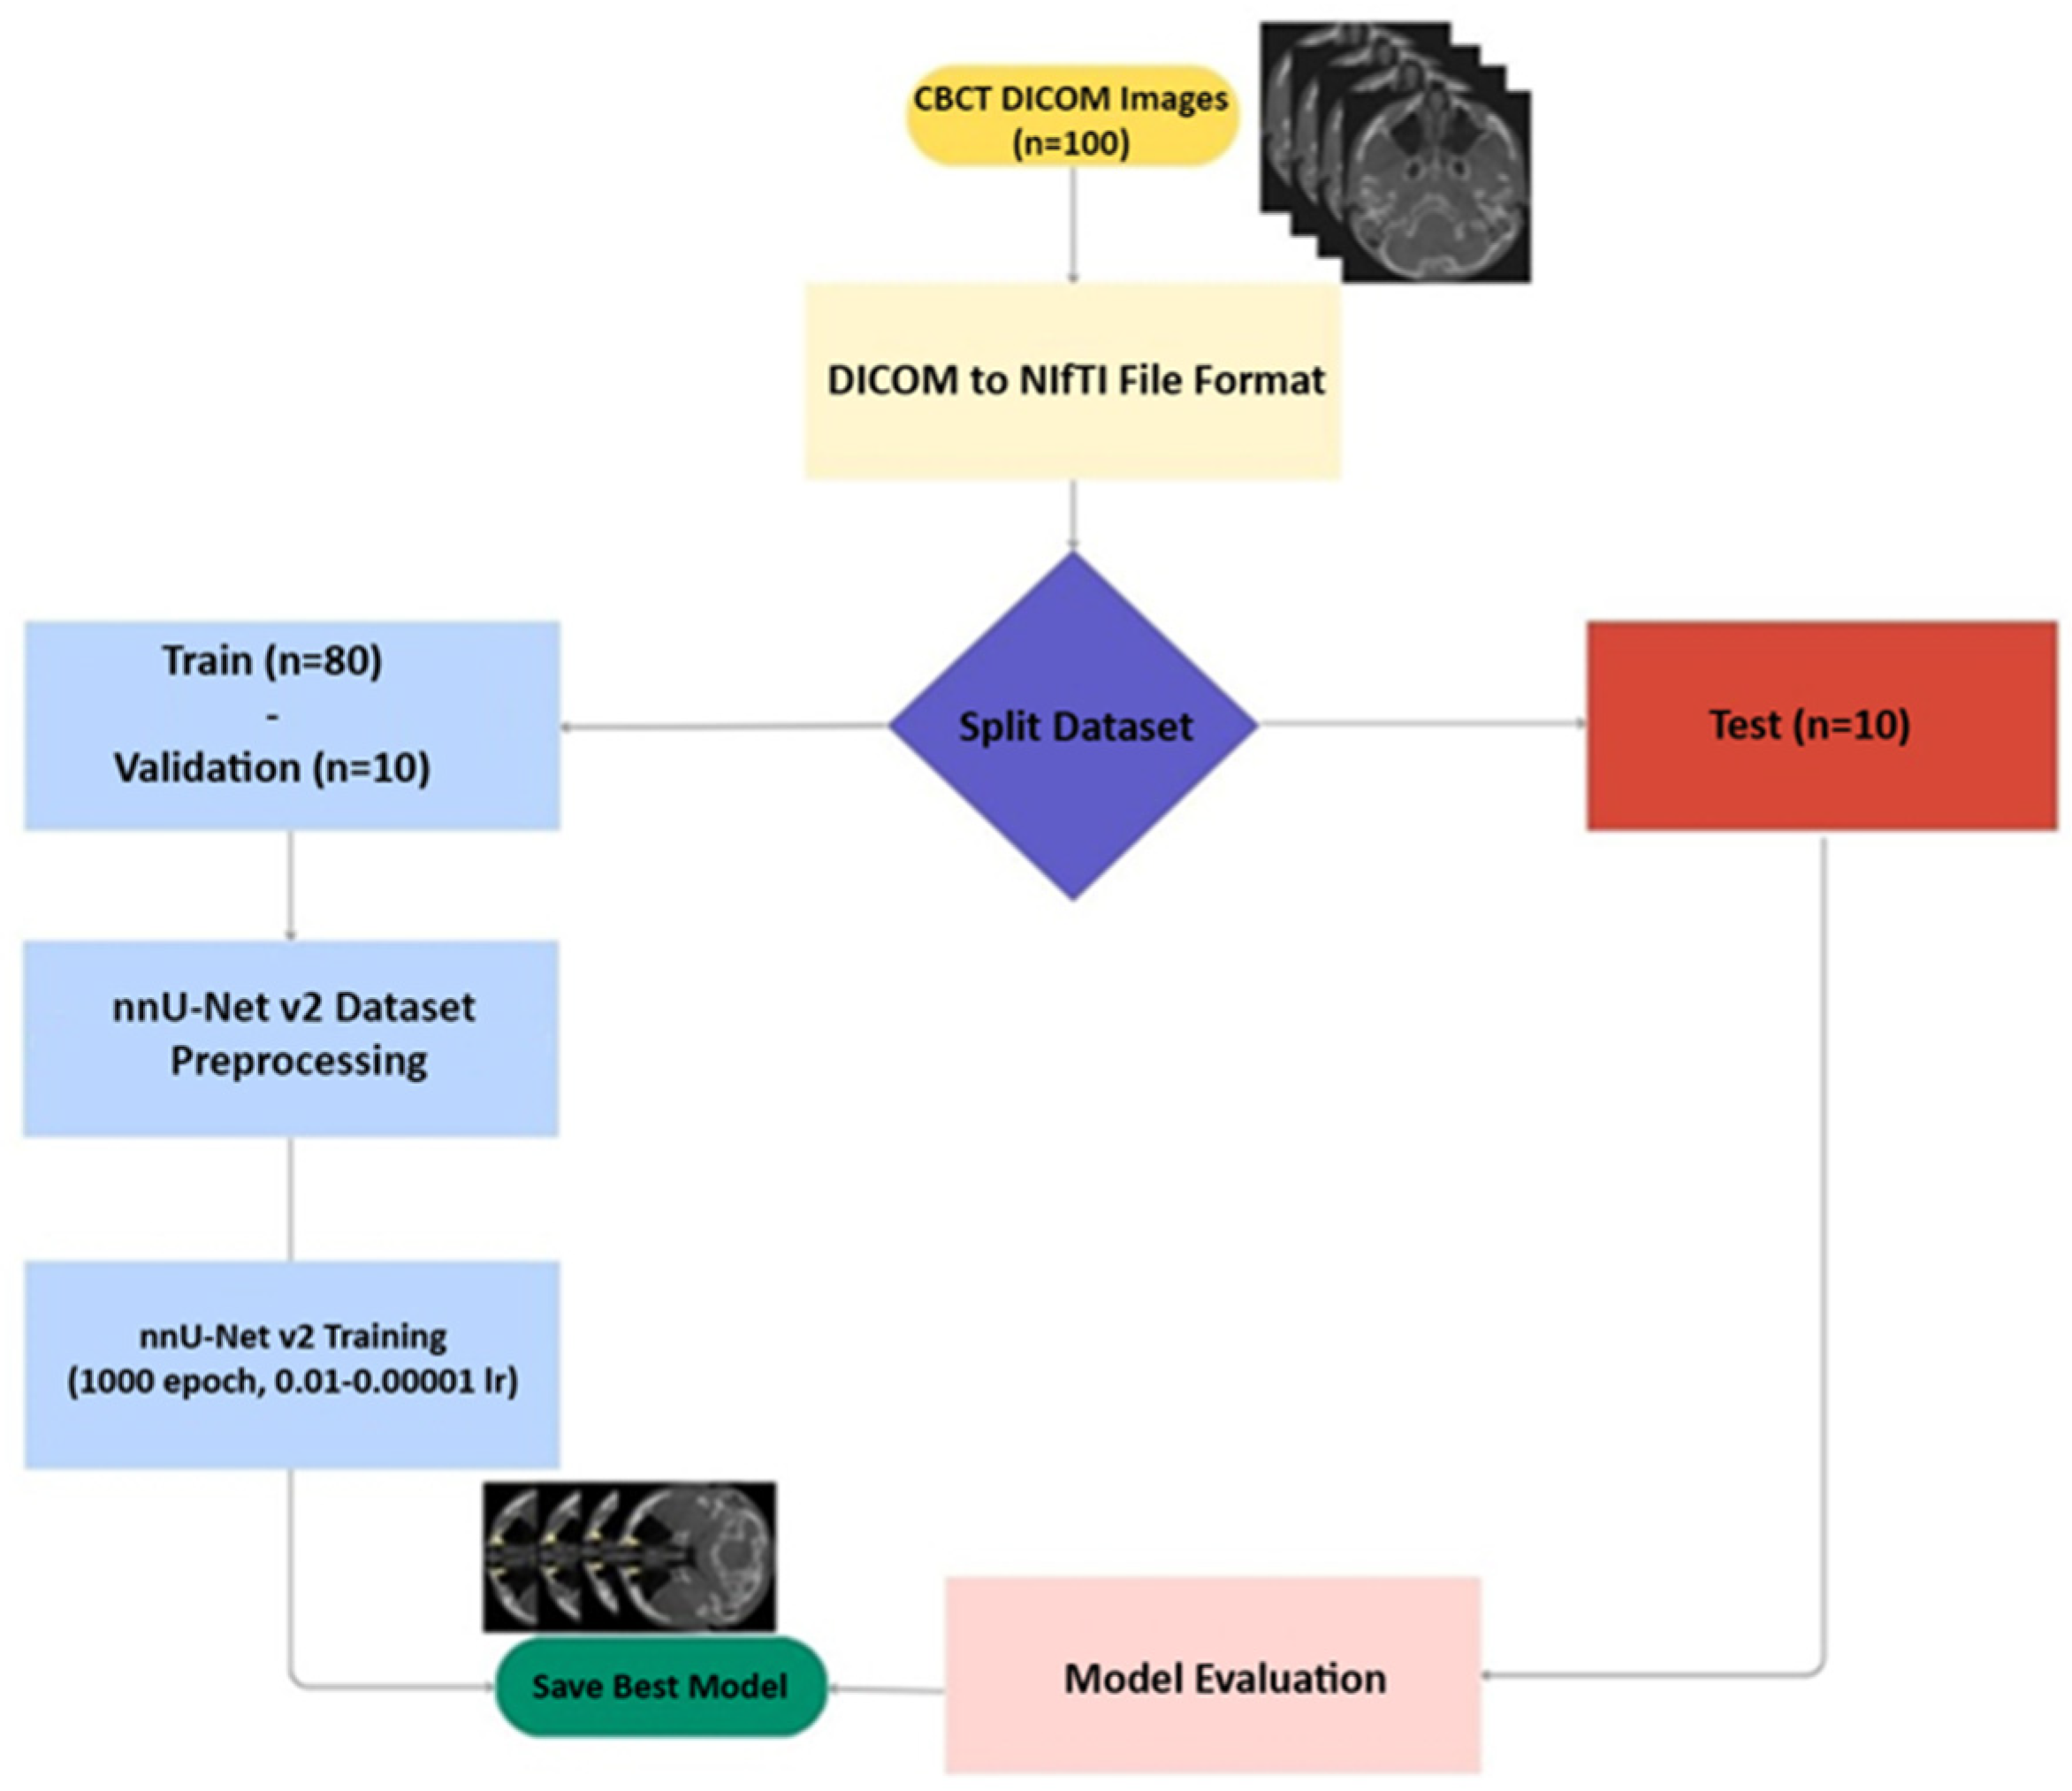

2. Materials and Methods

2.1. Study Design

2.2. Data

2.6. Model

2.7. Evaluation